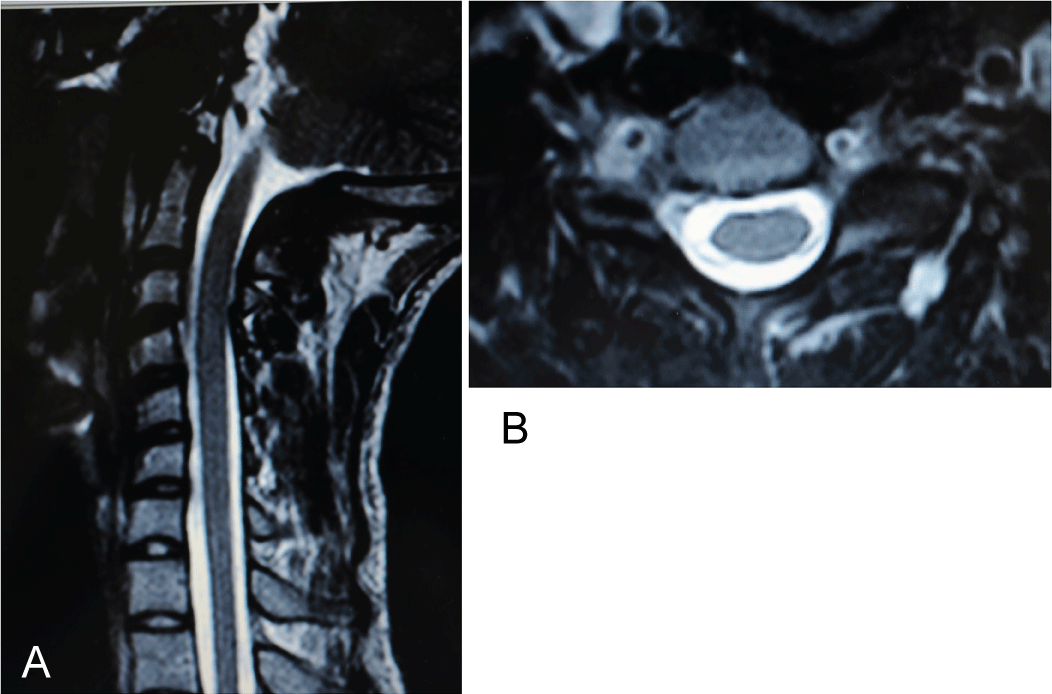

Figure 4: MR-scanning: a) Sagittal plane: A normal spinal cord in the cervical spinal canal; b) Axial plane: Spinal canal asymmetry was marked by a displaced spinal cord to the left (i.e., toward the concavity of the torticollis). View Figure 4

Figure 6: Postoperative MR-scanning (5 years) remained unchanged: Spinal canal deformity and the asymmetric position of the spinal cord towards the concavity of the torticollis are noted. View Figure 6